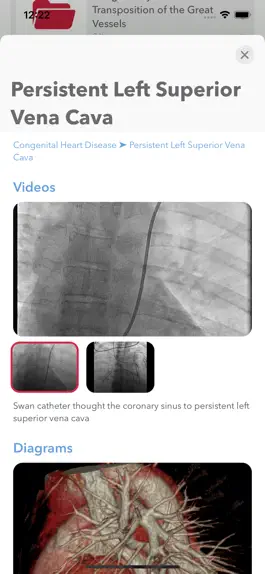

Скриншоты

Game screenshot Cathlas mod apkGame screenshot Cathlas apkGame screenshot Cathlas hack

Cathlas includes angiographic videos in various topics – for example:

• Images of congenital heart disease and right heart catheterization hemodynamics